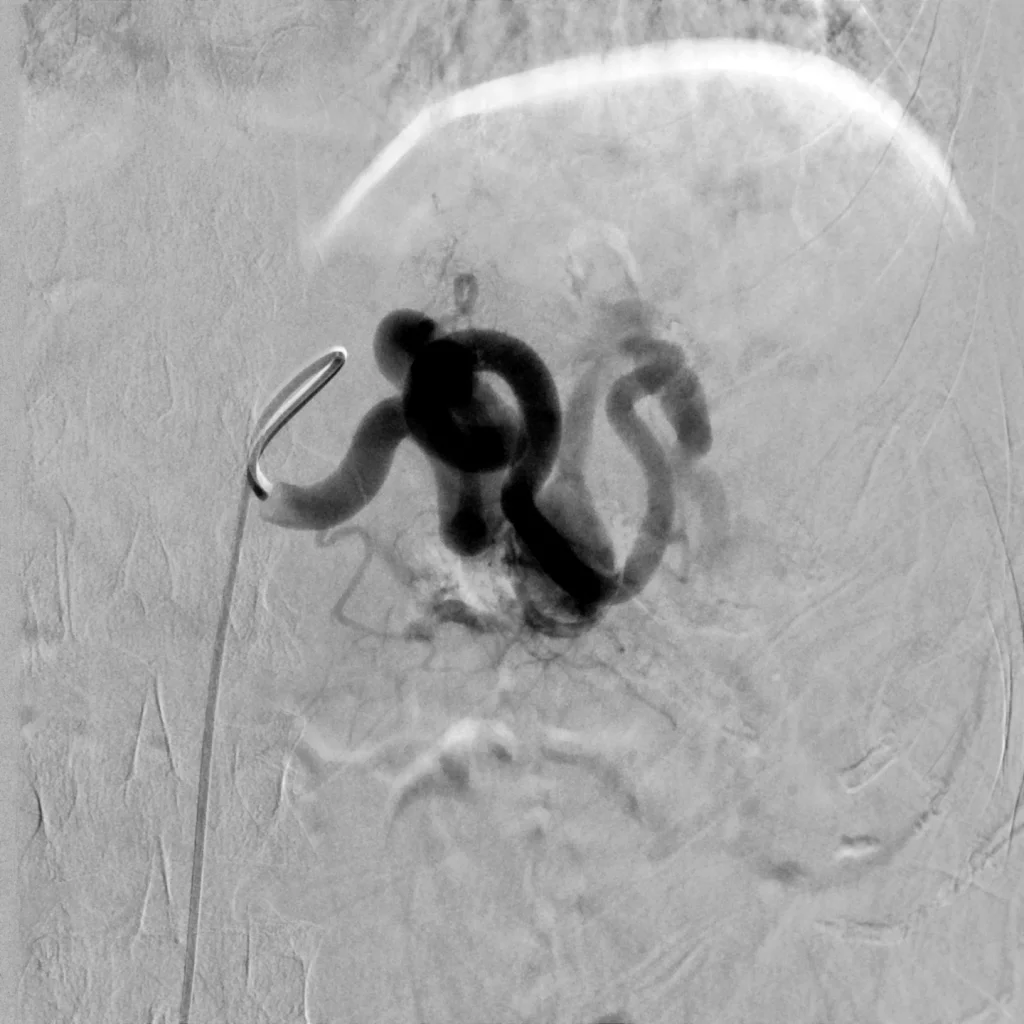

45 year old female patient who presents with ill-defined abdominal pain. A CT demonstrated a splenic artery aneurysm. Treatment was attempted from a femoral approach but the tortuosity of the splenic artery made it impossible to maintain a stable catheter position. As a result, radial access was obtained, and embolization was ultimately performed with multiple detachable coils.

Comment: This case demonstrates the importance of choosing the most appropriate access site given the demands of the procedure. In this case, the angle of the celiac axis favored a radial approach. By placing the sheath from a radial approach, the system was stable until the first curve of the celiac axis. The presence of the sheath enabled us to push the microcatheter forward in the splenic artery without buckling the sheath into the aorta. Ultimately, the microcatheter was advanced until it coiled within the aneurysm. Care was taken while embolizing to keep the coils more towards the inferior aspect of the aneurysm sac to maintain patency of the vessel arising from the apex of the aneurysm.